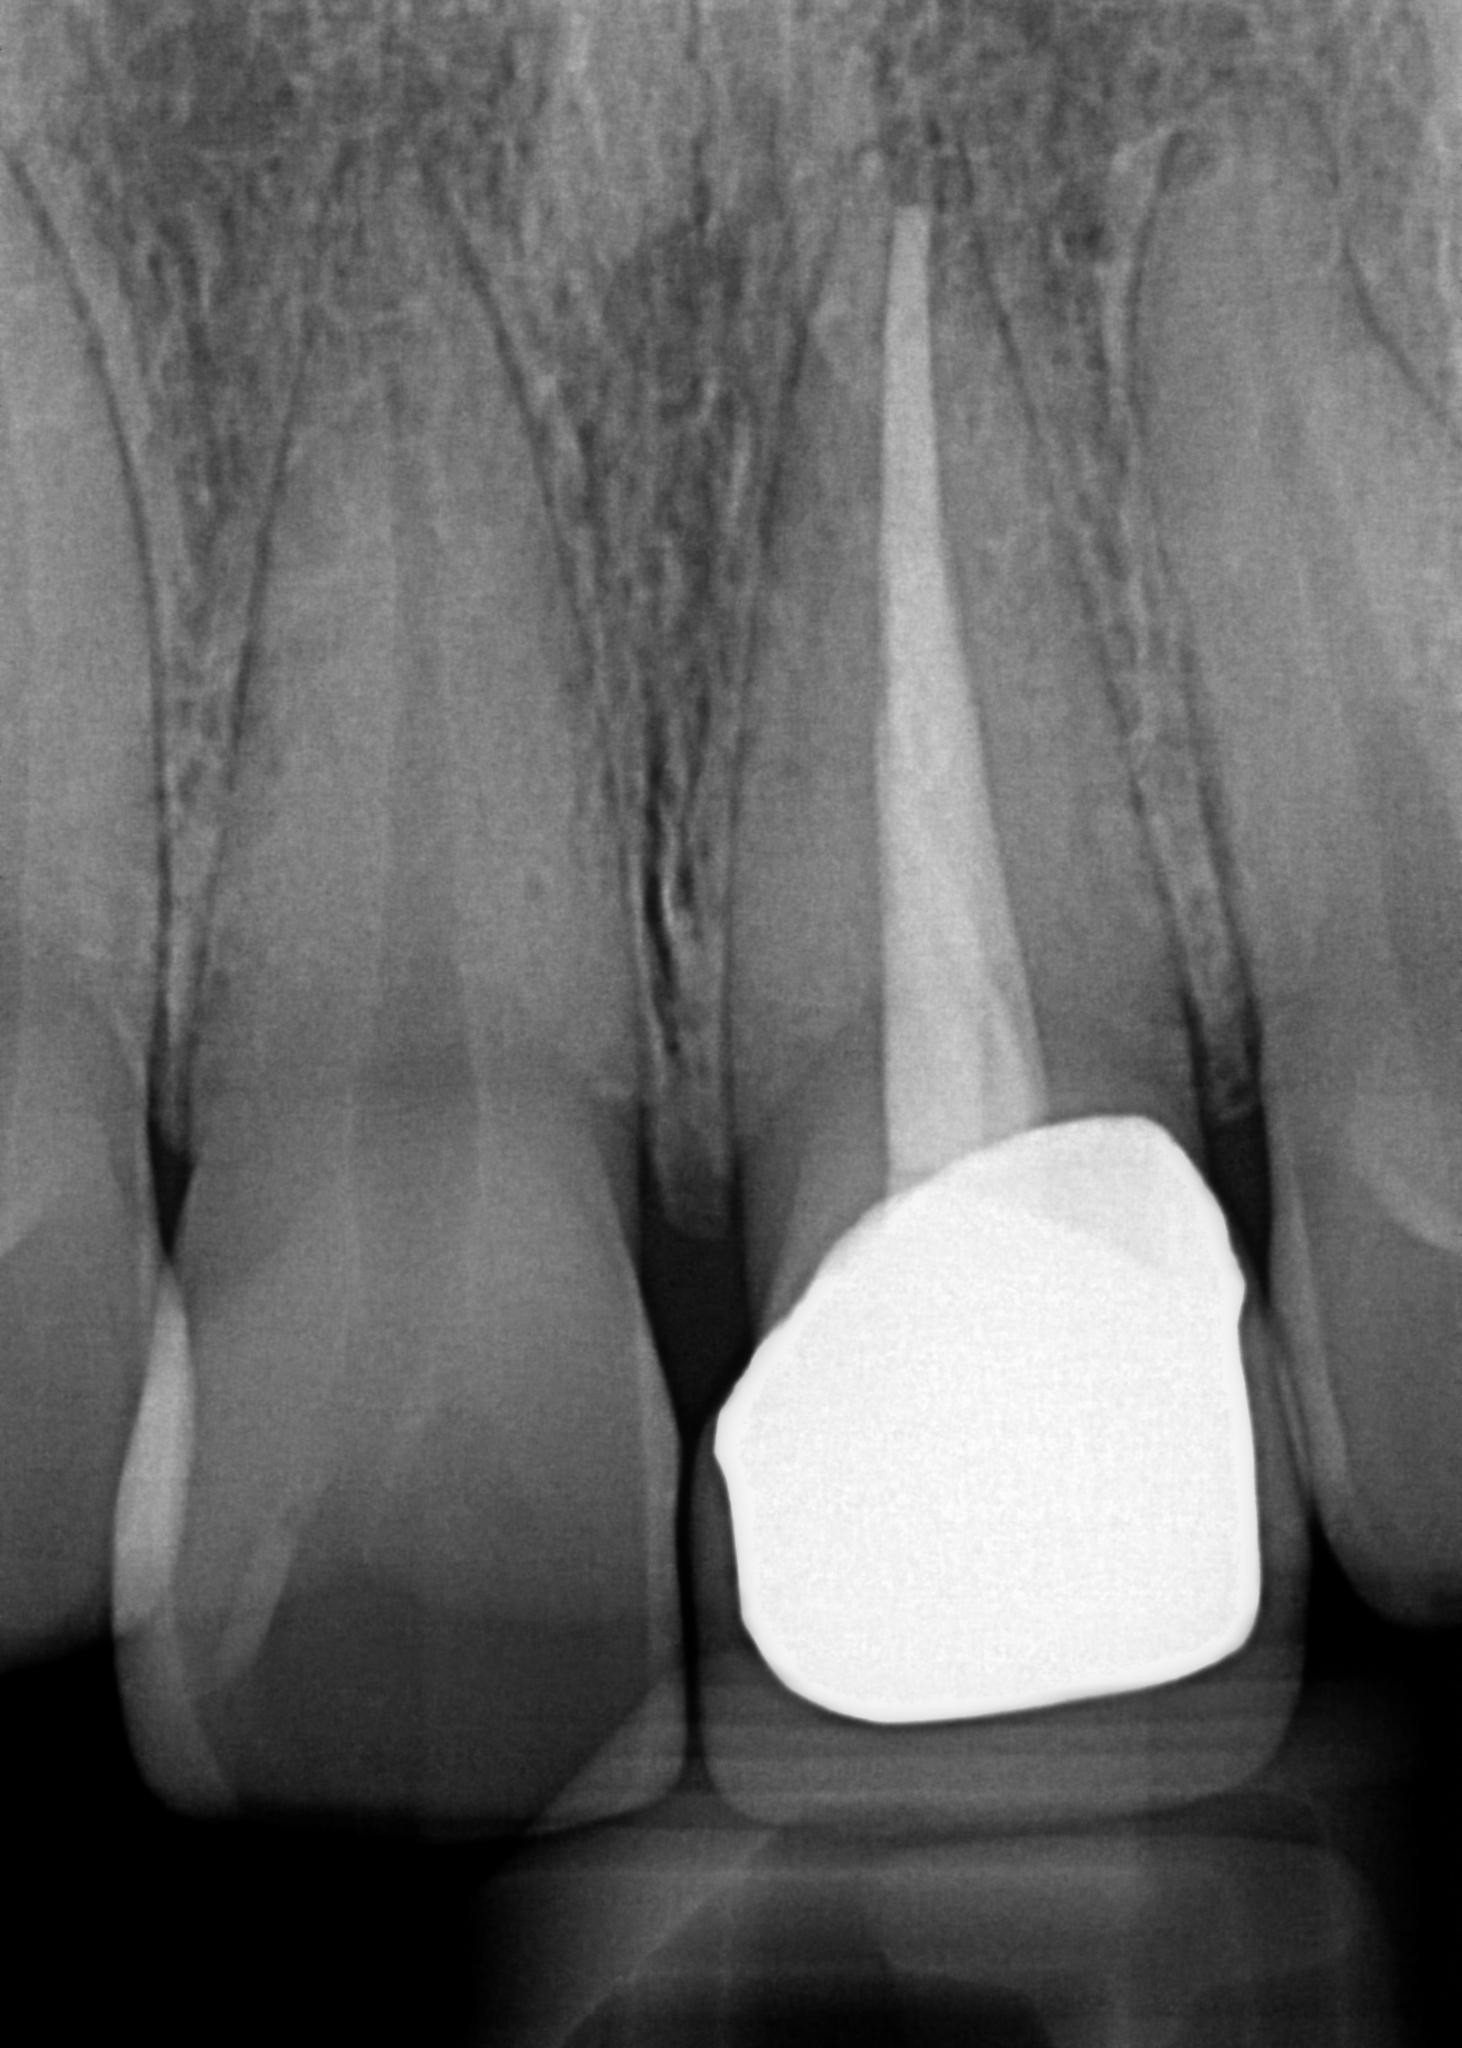

7. What option can explain the crown of the tooth #2.1?